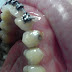

Estas fotos abaixo, são de uma criança do sexo masculino de 2 anos apenas.

A família, por estar desinformada oferece à criança refrigerante na mamadeira e não higieniza a boca da criança antes de dormir.